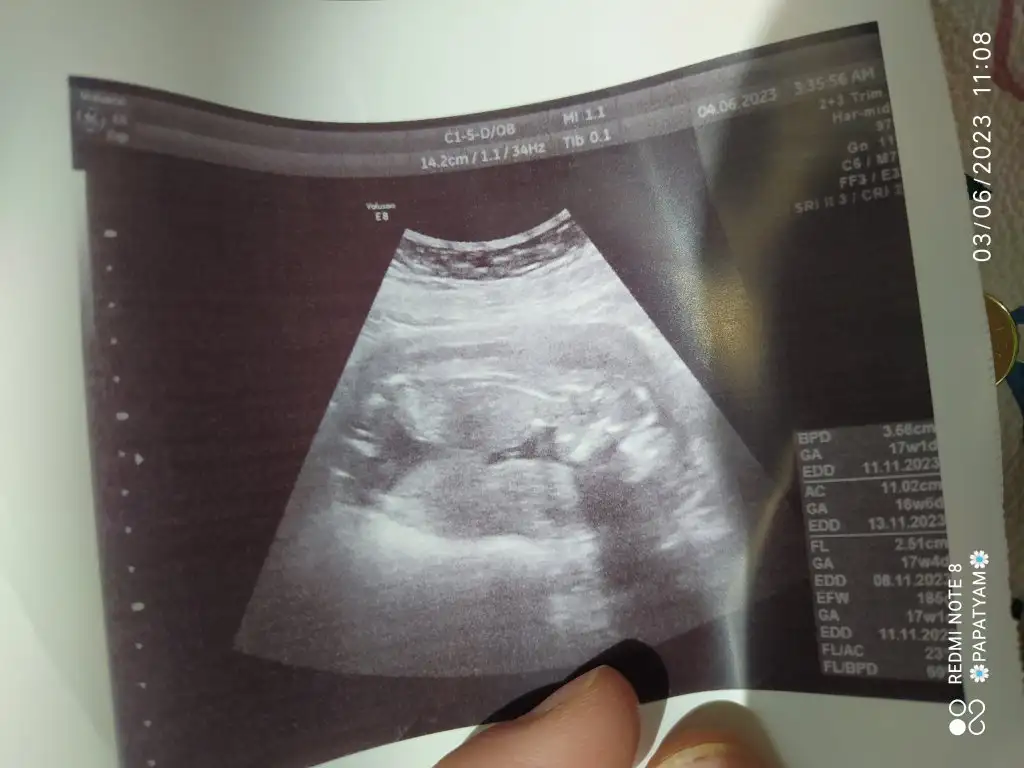

Teyzeleri, doktordan çıktık şimdi. Kızım çok utangaç olcak sanırım ellerini yüzünden hiç çekmedi. Doktor bir ara sarstı o ara sinirlenip çekti ellerini🙈 onun dışında her şey yolundaydı, boyu kilosu(220 gr🐣)